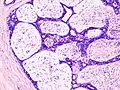

| Histopathologic image of breast fibroadenoma. Core needle biopsy. H&E stain. | |

Fibroadenoma of the breast is a benign tumor composed of a biplastic proliferation of both stromal and epithelial components.[12][13] This biplasia can be arranged in two growth patterns: pericanalicular (stromal proliferation around epithelial structures) and intracanalicular (stromal proliferation compressing the epithelial structures into slit-like spaces).

These tumors characteristically display hypovascular stroma compared to malignant neoplasms.[2][14][9] Furthermore, the epithelial proliferation appears in a single terminal ductal unit and describes duct-like spaces surrounded by a fibroblastic stroma. The basement membrane is intact.[15]

Fibroadenoma histology (H&E). The image demonstrates intracanalicular morphology (bottom left) and pericanalicular morphology (top right)